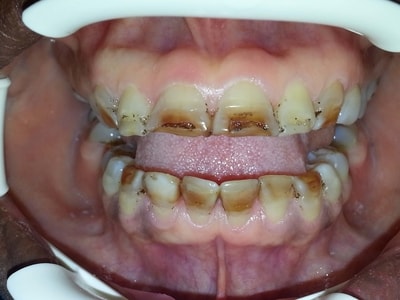

Cas numero 1 :

Situation Initiale